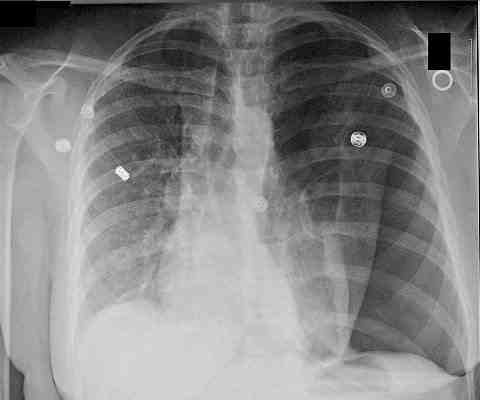

Ventilation/perfusion mismatch causing shunt. V/Q mismatch results when ventilation of areas of the lung is inadequate to fully oxygenate blood flow. Shunting occurs when blood passes though areas of the lungs that have no ventilation. Causes include, alveolar collapse and bronchial intubation.

Shunt will not be corrected by increasing the FiO2.